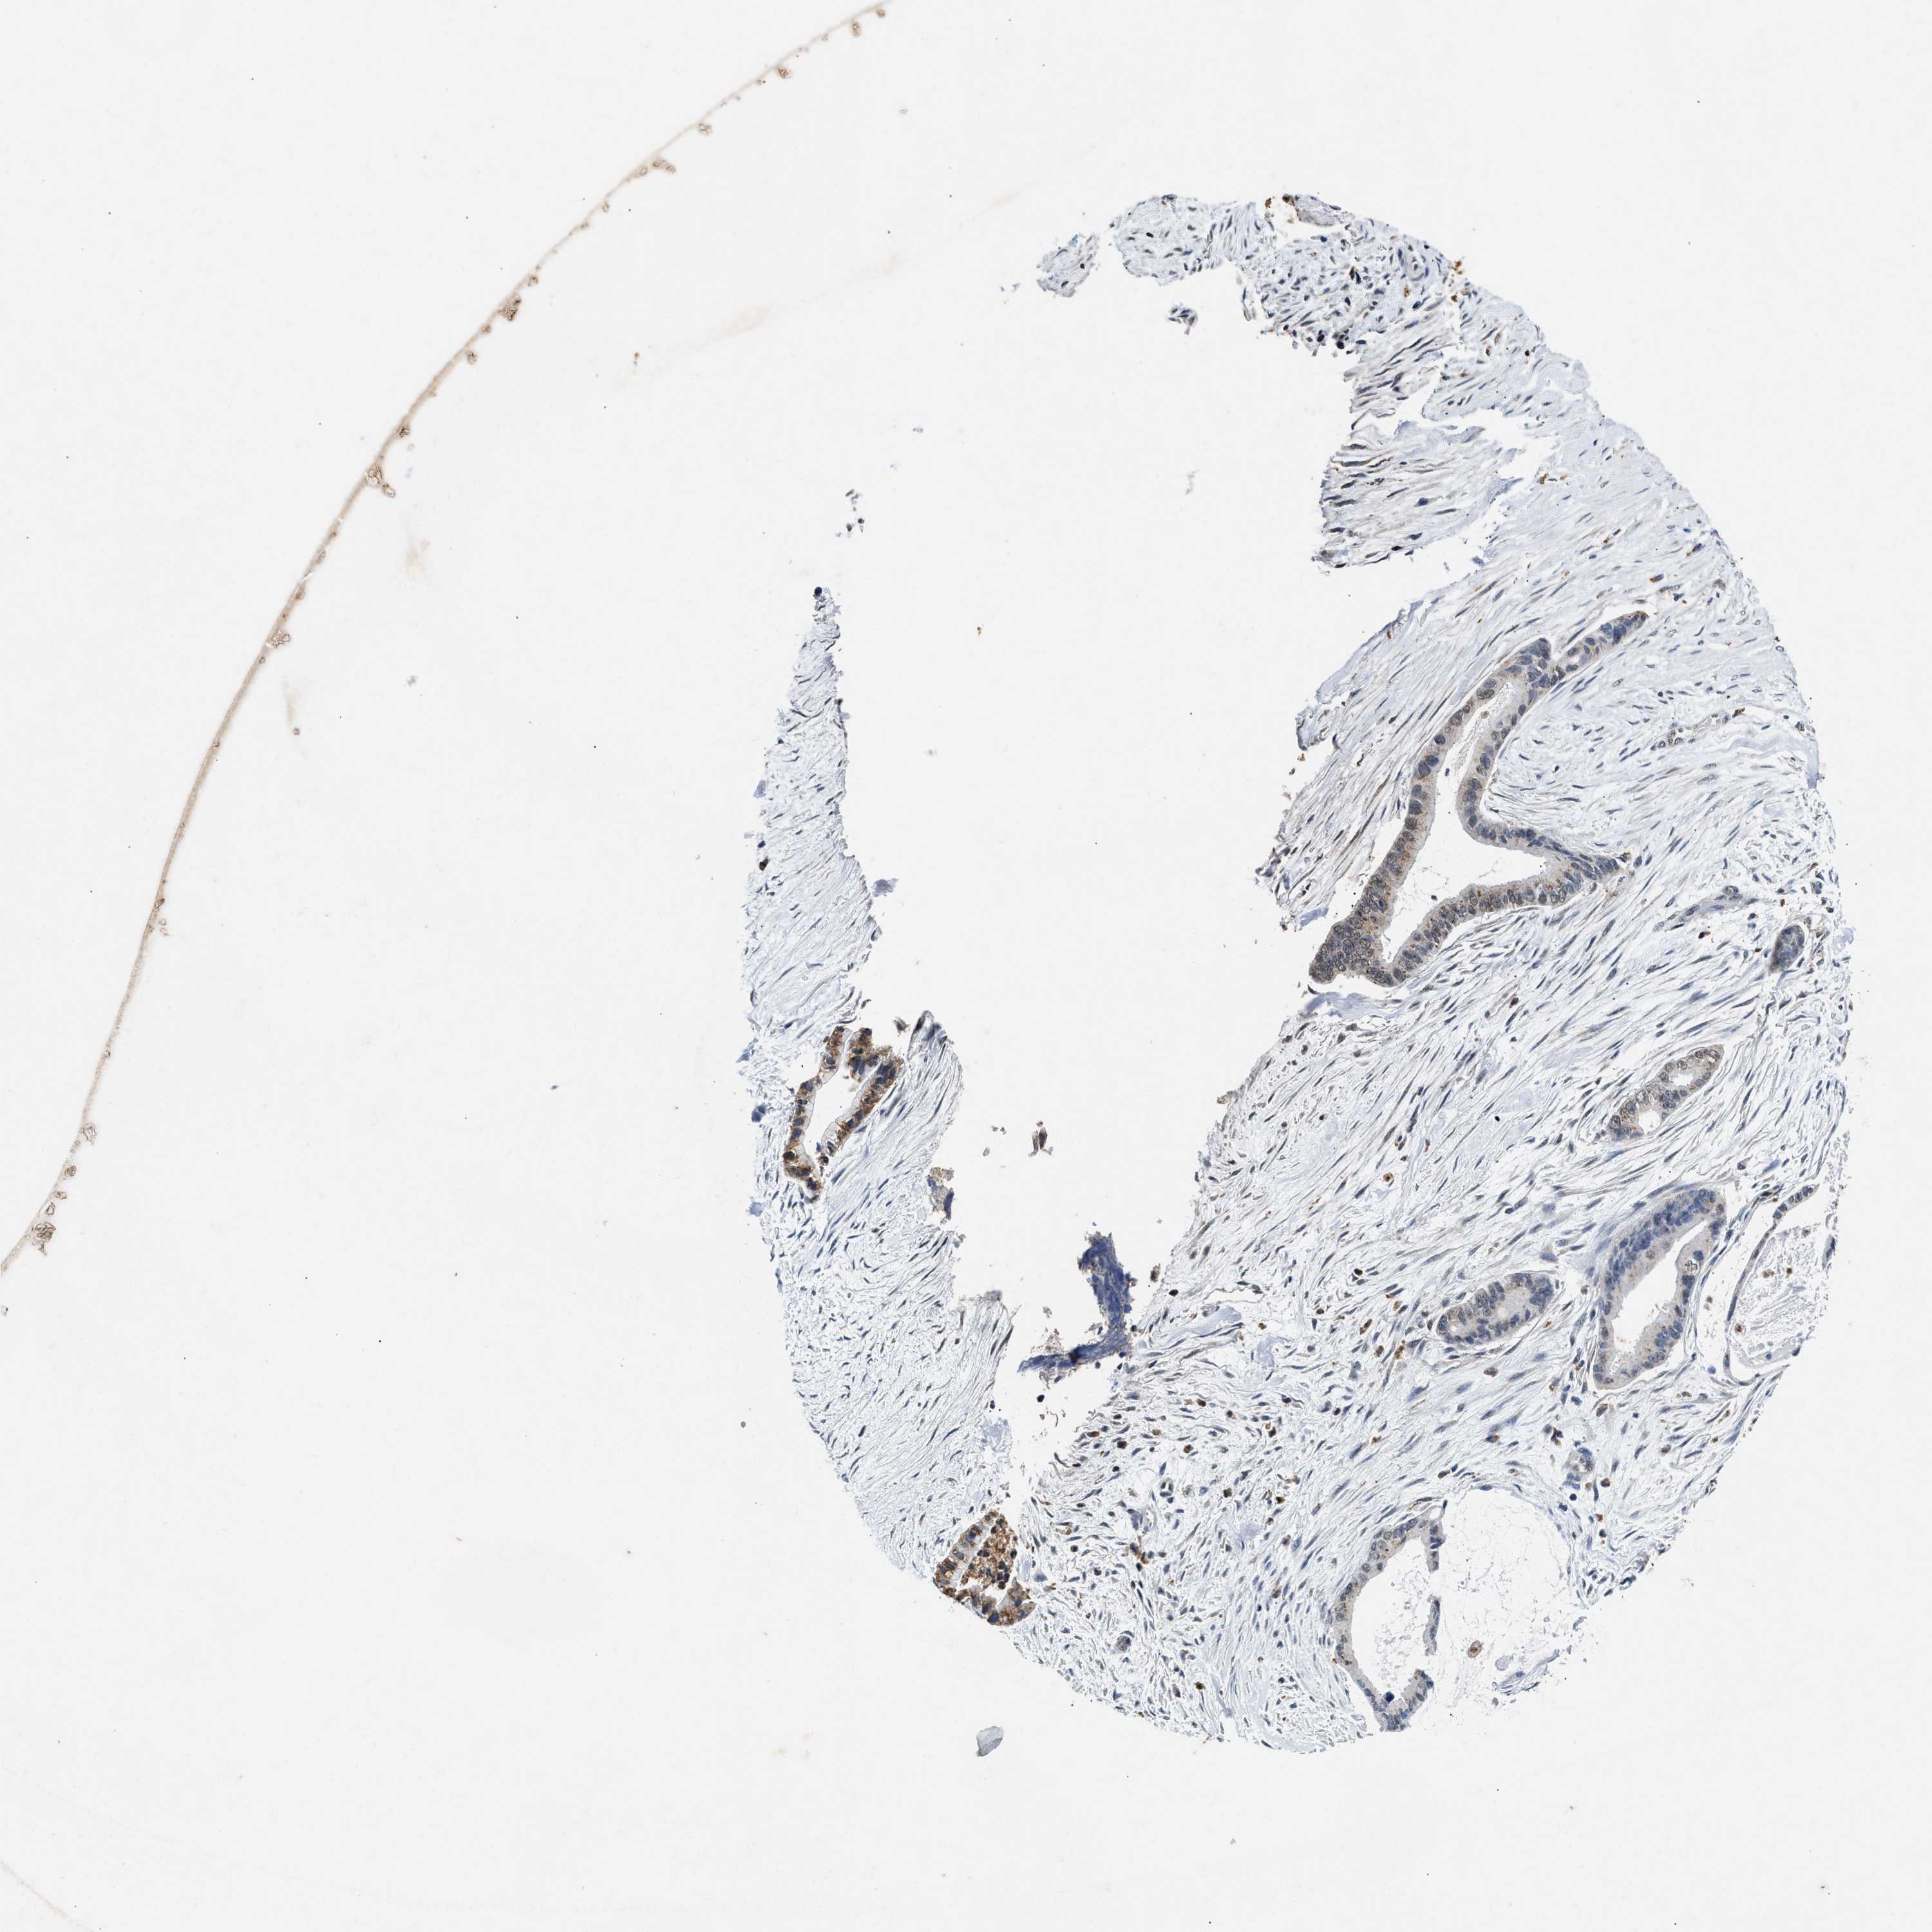

LIVER CANCER - Protein expressioni

A mouse-over function shows sample information and annotation data. Click on an image to view it in a full screen mode. Samples can be filtered based on level of antibody staining by selecting one or several of the following categories: high, medium, low and not detected. The assay and annotation is described here.

Note that samples used for immunohistochemistry by the Human Protein Atlas do not correspond to samples in the TCGA dataset.

Antibody stainingi

Antibody staining in the annotated cell types in the current human tissue is reported as not detected, low, medium, or high, based on conventional immunohistochemistry profiling in selected tissues. This score is based on the combination of the staining intensity and fraction of stained cells.

Each image is clickable and will lead to virtual microscopy that enables deeper exploration of all samples and also displays staining intensity scores, fraction scores and subcellular localization as well as patient and tissue information for each sample.

Antibody HPA021192

Antibody HPA021195

Antibody HPA028759

Antibody CAB021094

Staining

High

Medium

Low

Not detected

Intensity

Strong

Moderate

Weak

Negative

Quantity

>75%

75%-25%

<25%

None

Location

Nuclear

Cytoplasmic/membranous

Cytoplasmic/membranous,nuclear

Cholangiocarcinoma

Carcinoma, Hepatocellular, NOS